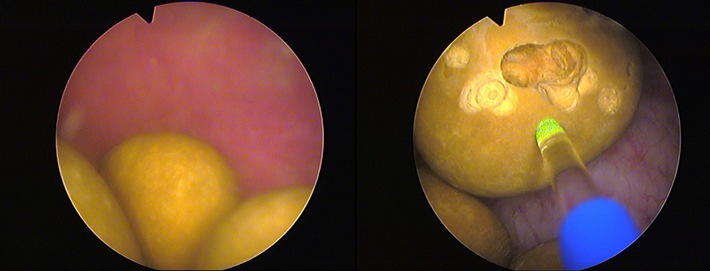

Die Klinik geht seit einigen Jahren einen anderen Weg: Statt der klassischen OP nutzt sie einen sogenannten Holmium-YAG-Laser des deutschen Herstellers Wolf aus dem schwäbischen Knittlingen zur Therapie. Die Faser eines 'MegaPuls 30+'-Lasers wird mittels Zystoskop, einem Instrument zur Blasenspiegelung, über die Harnröhre in die Blase geleitet und zerstört dort mit gepulsten Energiestößen von 200 bis 4000 Millijoule (mJ) die Blasensteine. "Wir durchfahren während der Behandlung ein Impuls-Spektrum von 3 bis 25 Hertz, da jeder Stein anders aufgebaut ist und jeder Stein bei einer anderen Impulsfolge zerplatzt", beschreibt der Martin Löhr das Verfahren. Jeder Puls ist dabei mit 150 bis 850 Mikrosekunden (µs, Millionstel Sekunde) extrem kurz. Der Stein-Laser bringt dabei eine Leistung von 30 Watt. Er arbeitet zwar auch mit einem grünen 532-Nanometer-Laserstrahl, doch dieser gilt nur als Orientierung für den Operateur; er ist quasi ein Pilotstrahl. Der eigentliche Impuls zur Zerstörung der Blasensteine kommt durch einen für das menschliche Auge unsichtbaren 2100-Nanometer-Laserstrahl.

Je nach Zahl und Größe der Blasensteine dauert eine Laser-Behandlung zwischen wenigen Minuten und einer Stunde. Da sich der Patient in einer leichten Narkose befindet, spürt er von alledem nichts.

Nach dieser Laser-Lithotripsie werden die Stein-Überreste abgesaugt oder fließen mit dem Harn ab. "Die für den Harnstau verantwortliche Prostata-Vergrößerung behandeln wir wenige Woche später sehr schonend mit unserem Greenlight-Laser, der mit seiner Leistung von 180 Watt auch Prostata-Drüsen von deutlich über 100 Gramm schafft", so Löhr. Das grüne Laserlicht trägt dabei das überflüssige Gewebe nach dem Prinzip der Photoselektiven Vaporisationschonend ab, so dass der Patient schon am Folgetag wiederhergestellt ist und seiner Arbeit nachgehen kann - ohne langwierige und belastende Operation mit gravierenden Nebenwirkungen. "Auch das Risiko einer Einschränkung der Potenz oder Zeugungsfähigkeit ist bei den beschriebenen Laser-Verfahren extrem gering", bestätigt Kollege Thomas Dill.